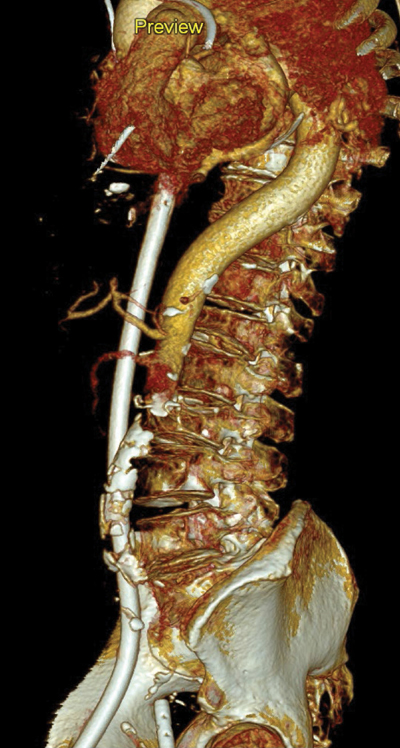

CTA demonstrated good opacification of the thoracic aorta up to the level of the superior mesenteric artery (SMA). However, more distally, no marked enhancement of the aorta and visceral vessels was obtained (Figures 3–5).

Figure 5

3D reconstruction of the watershed zone at the level of the superior mesenteric artery (SMA).

In this case, no luminal contrast opacification nor active haemorrhage distal to the SMA was present due to the watershed phenomenon, with the blurred area at the level of the SMA and despite the haemorrhage surrounding the right superficial femoral artery.

Since distal to the SMA no vascular enhancement was obtainable, active bleeding could not be ruled out. Awareness of the watershed phenomenon is crucial, since artefacts can be mistaken for pseudolesions such as thrombus, dissection, or vascular occlusion. The watershed area can also potentially obscure true pathology [2], with potentially fatal consequences, as in this case where an active bleeding could be overlooked.